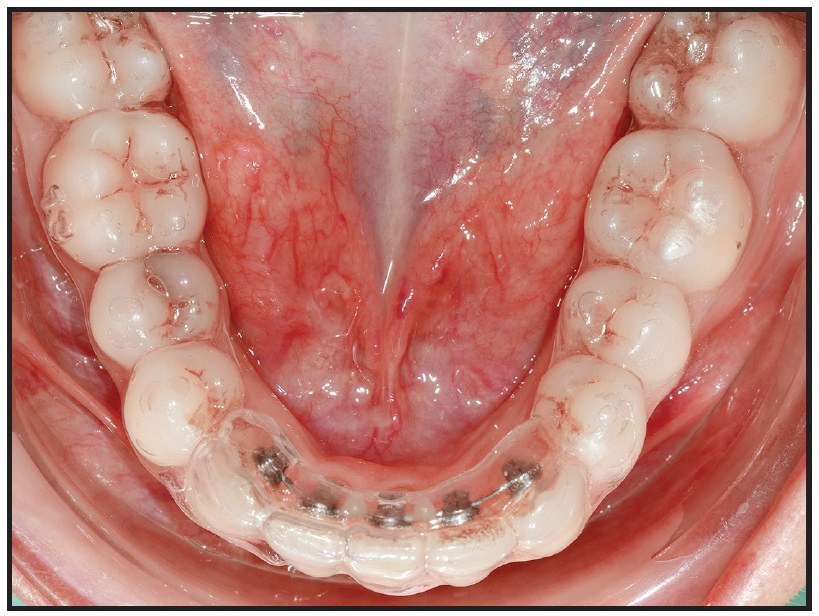

Clinicians can also use partial appliances with clear aligners in the same arch, as is commonly done when treating mesioangular lower second molars. In this instance, the labial appliances are placed only on the premolars and molars for insertion of a segmental nickel titanium wire, while the terminal end of the clear aligner extends just over the most anterior bracketed tooth (Fig. 2). Most recently, anterior lingual appliances have been used underneath full-arch clear aligners to reinforce their prescribed movements (Fig. 3).2

Fig. 2 Partial labial appliance for molar uprighting after protraction of upper left second and third molars; note that upper clear aligner partially covers upper left second premolar.